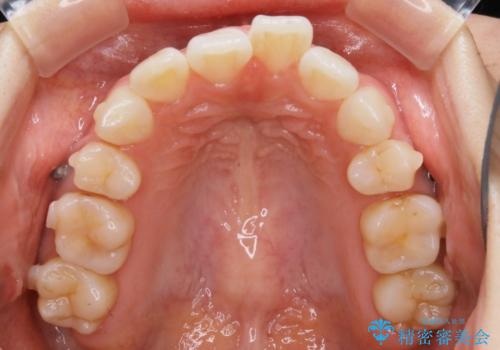

- 以前、中学生から高校生にかけてワイヤー装置による抜歯矯正を経験されている患者さんで、大人になってからのライフスタイルの変化でリテーナーを継続使用することができず、ガタつきが目立つようになってきてしまったのでもう一度矯正治療がしたいという主訴でご来院されました。

既に上下左右の4番目の歯が抜歯されているため、今回の治療では抜歯をせず歯の移動だけでガタつきを治す必要があり難易度が高くなっていました。